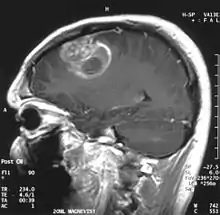

- L'imagerie par résonance magnétique est trop peu sensible pour représenter le passage de substances actives à travers une barrière hémato-encéphalique saine. En cas de lésion, l’IRM avec produit de contraste joue un grand rôle.

D'autres pathologies peuvent perturber le fonctionnement des endothéliums « du dedans vers le dehors », c'est-à-dire que des influences provenant de la matrice extracellulaire perturbent l'intégrité de la barrière hémato-encéphalique. Par exemple, on a le glioblastome[53].

Le premier produit de contraste mis au point pour l'IRM est le gadolinium (Gd). En raison de sa toxicité, il faut l’emballer (le chélater) dans une molécule de DTPA. On a ainsi obtenu en 1984 le Gd-DTPA[81], qui avait le potentiel pour obtenir des IRM renforcés pour le diagnostic de lésions locales de la barrière hémato-encéphalique[82]. La molécule de Gd-DTPA est très polaire, et par conséquent bien trop hydrophile pour traverser une barrière hémato-encéphalique saine. Les modifications des jonctions serrées, comme celles qui peuvent par exemple être provoquées par un glioblastome, permettent le transport paracellulaire de ce produit de contraste dans le tissu cérébral. Là, il renforce le contraste, par interaction avec les protons de l'eau environnante, et rend visibles les défauts de la barrière hémato-encéphalique. Comme ce sont les vaisseaux responsables de l'alimentation de la tumeur qui sont touchés, dans son voisinage immédiat, on peut en apprécier l'extension.